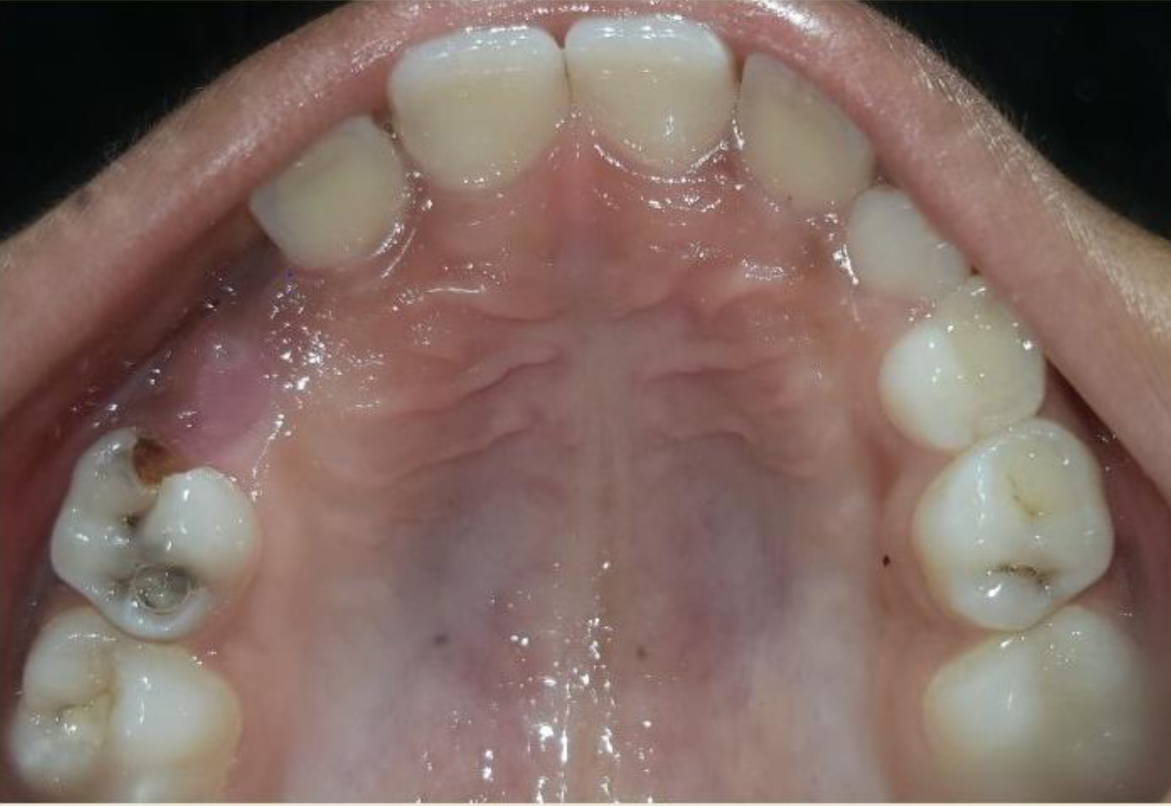

A nine year old boy reported to the Department of Pedodontics and Preventive Dentistry of Bharati Vidyapeeth Deemed University, Sangli with a chief complaint of pain and abscess in the lower left back region of the jaw since one month. Patient was a known case of autism spectrum disorder. He was inattentive, hyperactive and showed repetition of gestures. Psychological testing report showed childhood autism rating scale (CARS) 2, which falls into mild to moderate autistic category. Vineland social maturity scale (VSMS) measuring the social intelligence of child was found to be 31.5 with social age of around 5-6years. The family history was non-contributory. He was not on any medications and had reported no history of drug allergies. Extra-oral examination showed no specific findings (Figure 1). Intraoral examination revealed multiple carious lesions (Figure 2) (Figure 3). Occlusal caries involving enamel, dentin and pulp with 55 and 75. Intra oral dentoalveolar abscess was also seen in relation with 75 (Figure 4). Dentinal caries was seen with 85 and occlusal pit and fissure caries was seen with 65. No soft tissue abnormalities were appreciated. Radiographic evaluation by orthopantomogram was also done which revealed no abnormality (Figure 5). It was difficult for the patient to co-operate on the dental chair and understand the instructions given to him; hence treatment was planned under general anaesthesia. A complete pre anaesthetic evaluation was done and the patient was categorized under ASA II. Treatment plan was explained to the child’s parents and a written consent was obtained from them. The dental treatment done under general anaesthesia included pulpectomy of 55, 75 with glass ionomer cement restoration followed by placement of pre trimmed and pre contoured stainless steel crowns (Figure 6) (Figure 7). Glass ionomer cement restorations were done in 65 and 85 and pit and fissure sealants application on 16, 26, 36 and 46. Post-operative orthopantomogram showed well placed restorations and crowns (Figure 8). Patient’s post-operative recovery was uneventful. Treatment rendered reduced the pain and discomfort.Oral hygiene care instructions were given to the parents and maintenance protocol was explained and they were also encouraged for regular follow-up for preventive dental care. The two months follow-up revealed improved eating habits of the child.

Figure 3 Intra oral pre-operative image of the mandible.

Figure 7 Stainless steel crown cemented on 75 and glass ionomer cement restoration on 85 and Sealants on 36, 46.